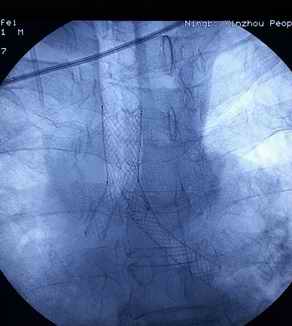

今日,我科为一肿瘤晚期患者成功进行了Y型支架植入术。该患者为肺癌晚期患者,经多次放化疗,效果不佳,肿瘤严重阻塞患者气管,支气管,危及生命。我科经过会诊,决定给予Y型支架植入术缓解患者症状,挽救患者生命。患者全麻下,由俞万钧副院长主刀,经历半小时,成功放置Y型支架,患者术后症状明显缓解,生活质量大大提高。我科已多次为肿瘤晚期患者行Y型支架植入术(徐涛)

图片1